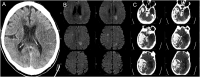

Results: 14.1% of admitted COVID-19 patients had neuroimaging and this accounted for only 5.5% of the total imaging studies. Acute stroke was the most common finding on neuro-imaging, seen in 92.5% of patients with positive neuro-imaging studies, and present in 1.1% of hospitalized COVID-19 patients. Patients with acute large ischemic and hemorrhagic stroke had much higher mortality risk adjusted for age, BMI and hypertension compared to those COVID-19 patients without neuroimaging. (Odds Ratio 6.02 by LR; Hazard Ratio 2.28 by CRR).

Conclusions: Our study demonstrates acute stroke is the most common neuroimaging finding among hospitalized COVID-19 patients. Detection of an acute stroke is a strong prognostic marker of poor outcome. Our study also highlights the fact there is limited use of neuroimaging in these patients due to multiple logistical constraints.